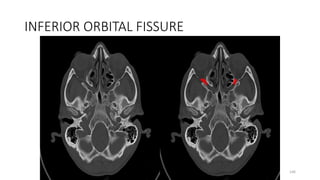

Inferior orbital fissure